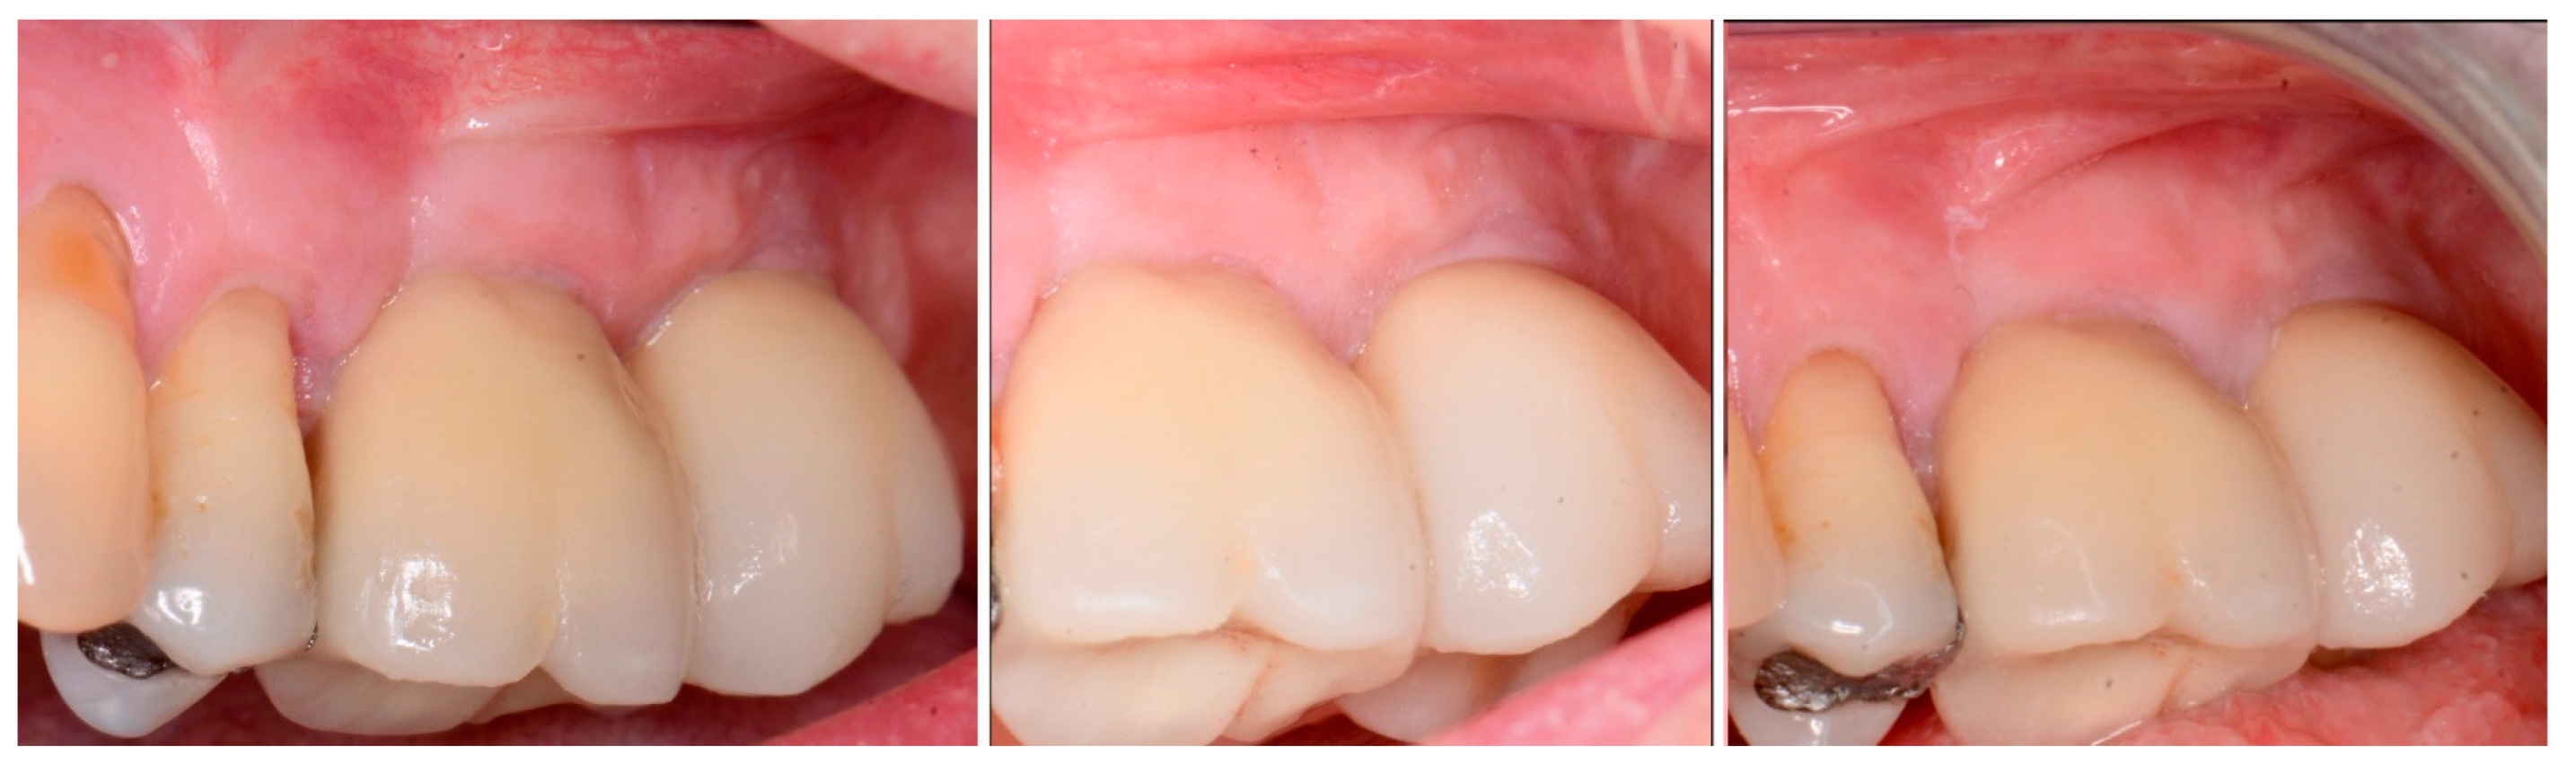

Figure 14.

Soft tissue at placement of the restoration on the 2nd molar (left), at 1 year post-restoration (middle) and at 2 years post-restoration (right) demonstrating maintenance of the keratinized tissue long term.